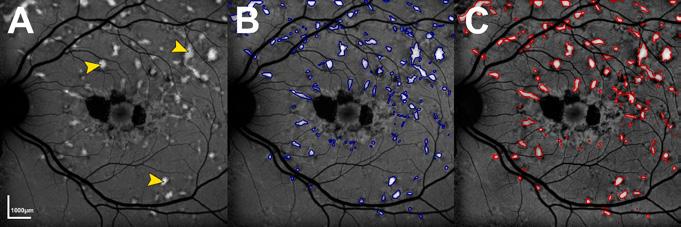

The retina, a light-sensitive layer at the back of the eye, is responsible for processing light signals crucial for vision. With multiple sublayers and cell types, it is one of the most intricate structures in the human body. Eye care health professionals use a variety of imaging techniques in order to assess its structure and function. Central (Figure 1A)

and wide-field (Figure 1C) photographs capture en face views of the retina, while cross-sectional scans, such as optical coherence tomography (OCT), reveal retinal sublayers (Figure 1B). Different wavelengths of light can also be used to infer retinal health and metabolism (Figures 1D and 1E).

Figure 1: A healthy retina imaged by different modalities. (A) Photograph of the central retina. (B) Optical coherence tomography, demonstrating various retinal sublayers. (C) Widefield pseudocolour photograph. (D) Fundus autofluorescence image of the central retina using short-wavelength light. (E) Fundus autofluorescence image of the central retina using near-infrared light.

AI has already shown promise – for example, in Stargardt disease, where bright hyperautofluorescent flecks are a key clinical feature. AI algorithms have been utilised to automatically detect and outline these flecks, with accuracy approaching that of expert clinicians. This demonstrates not only the feasibility of AI in IRD, but also its potential to accelerate and scale diagnostic processes. There has also been a rise in XAI, particularly in healthcare, where transparency and trust are as important as accuracy. By opening up the ;black box’ of AI, XAI helps clinicians to understand why an AI model makes particular predictions. This allows better translation of complex data into meaningful patient care.

Figure 2: Example of artificial intelligence (AI)-facilitated segmentation of hyperautofluorescent flecks in Stargardt disease. (A) Short-wave autofluorescence image of an eye with Stargardt disease. Pointers indicate examples of hyperautofluorescent flecks. (B) Flecks segmented by an AI algorithm. (C) Manually segmented flecks.